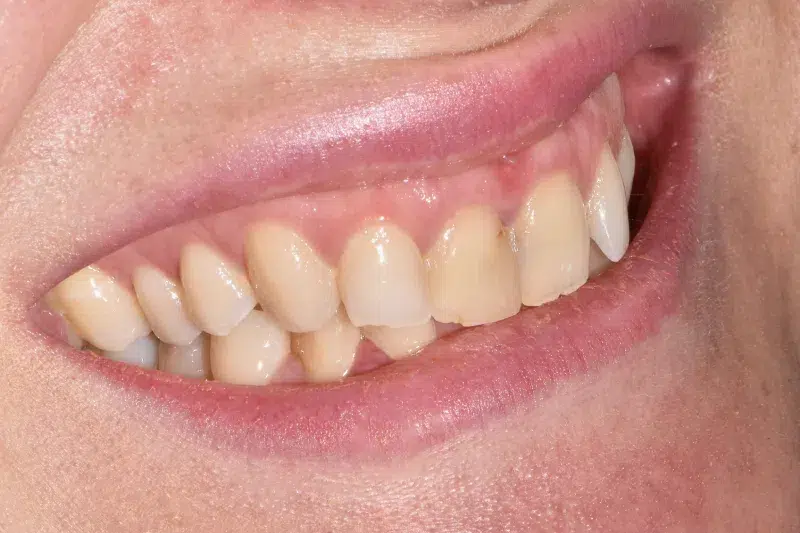

Caz de estetică dentară – Fațete ceramică presată E-Max

Provocarea acestui caz a fost în prepararea minim invazivă a dinților centrali rotați și a obține o formă și o culoare cât mai naturală, pacienta dorind un caz de estetică dentară ce să nu fie observabil.

Pacienta a beneficiat de corecție gingivala cu laser pentru uniformizarea asimetriilor gingivale, tratamente endodontice de canal sub microscop, obturațiile vechi (plombe) schimbate cu materiale de compozit cu particule nanoceramice, și fațete dentare din ceramică presată E-Max.

Termen de finalizare 2 săptămâni de la amprentarea finală.